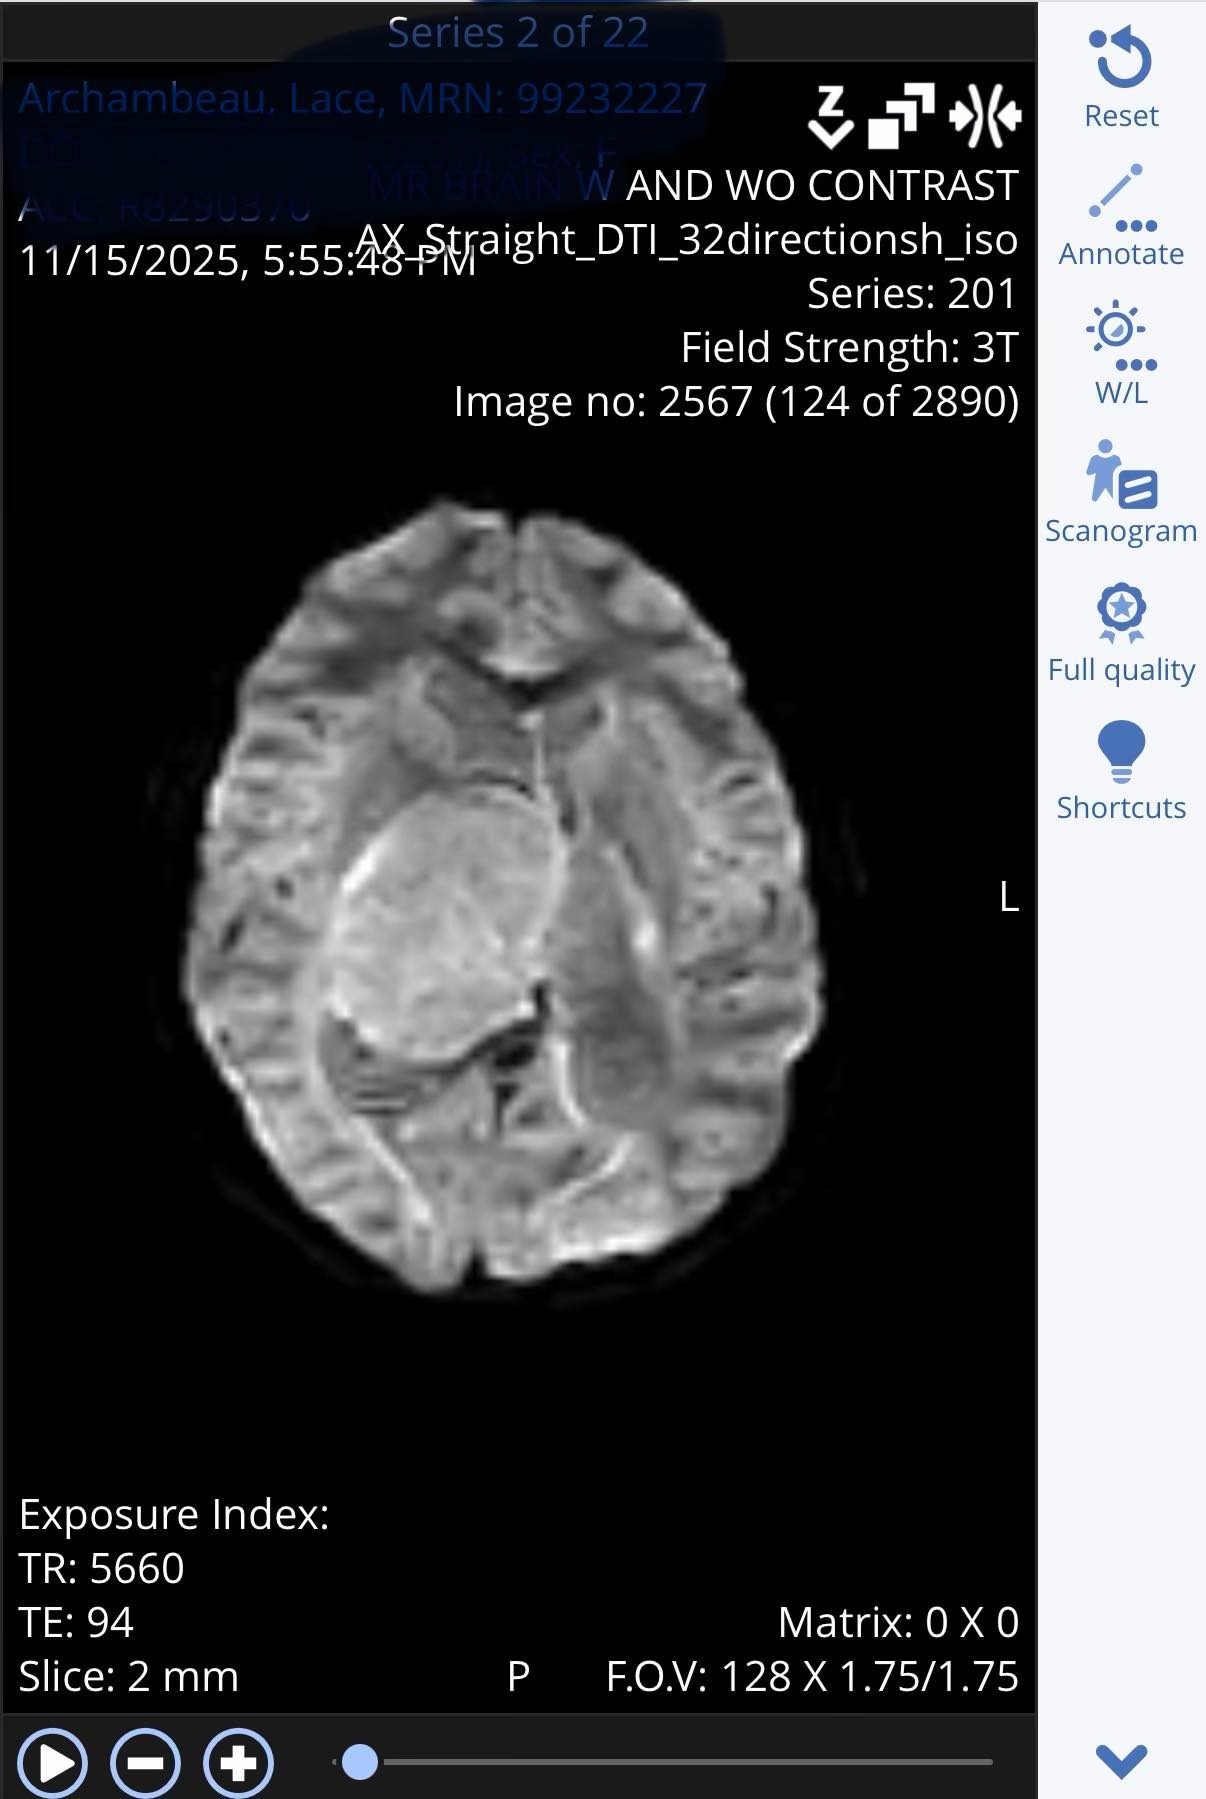

What began as a trip to the ER quickly revealed a large and aggressive brain tumor located deep within Lace’s brain. Because of the tumor’s size and location, doctors have been unable to remove it completely without risking vital brain function. Lace has already undergone complex brain surgery, ICU stays, and extensive neurological care. While only a portion of the tumor could be safely removed, her fight is far from over.